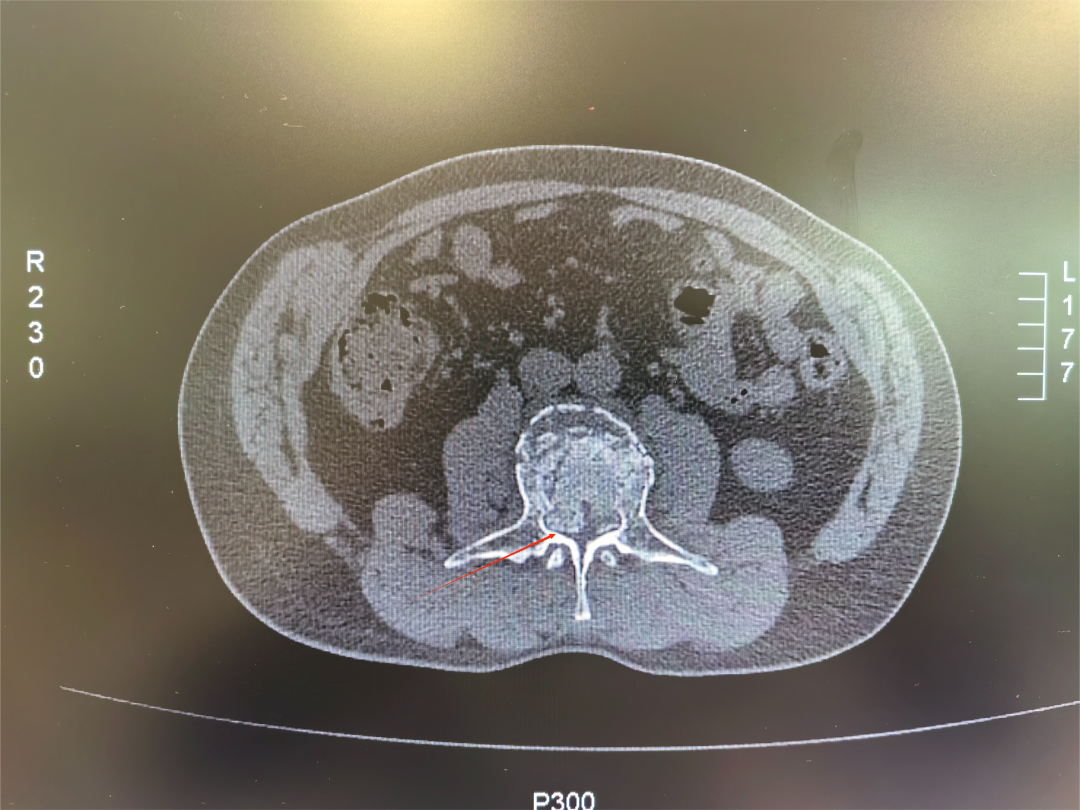

该患者为一名52岁中年男性,在工作时不慎从高处坠入3米深坑中,重伤腰部,被紧急送至西安市中心医院经开院区急诊科。急诊科请骨科张强医师紧急会诊,张强医师对患者进行详细查体后,第一时间要求完善患者相关腰椎X线、腰椎CT三维重建及腰椎MRI等检查,及时向刘邦定主任进行汇报,入院时,患者双下肢已完全不能活动,感觉减弱,情况万分危急。经过紧急CT及核磁共振检查,被确诊为“腰3椎体爆裂性骨折伴不全瘫痪”,碎裂的骨块如同“炸弹的弹片”一样,严重侵入椎管,压迫了支配下肢感觉和运动的脊髓神经。这正是导致患者瘫痪的直接原因。